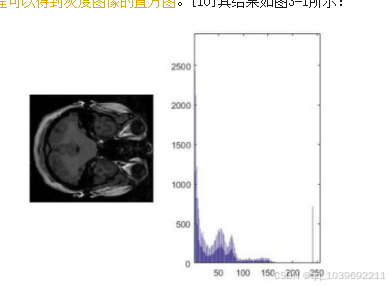

编程可以得到灰度图像的直方图。[10]其结果如图3-1所示:

图3-1 灰度图像直方图

在MATLAB软件中,计算灰度图像灰度分布范围。程序运行后,输出结果如图3.1所示。图3.1左图为灰度图像,

右图为灰度图像的直方图。从直方图可以看出,灰度图像的灰度值主要集中在0~160之间,所以图像呈现模糊状态。

如果把灰度值在0160之间均匀分布到0255之间,图像会变得更清晰。同时,需要将大于160的灰度值赋值为255。